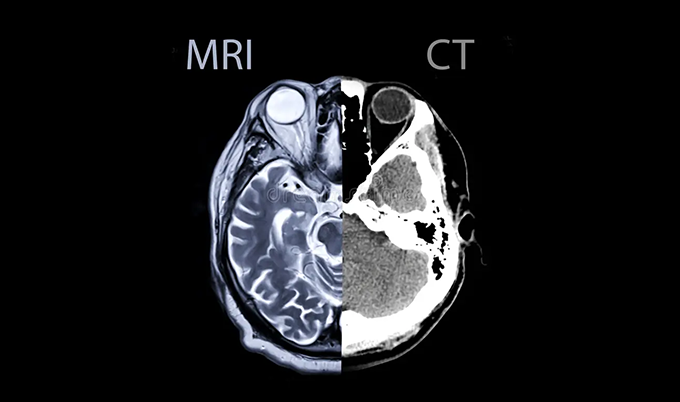

Emergency departments use two primary imaging technologies for acute stroke diagnosis requiring rapid stroke brain scan completion. The choice depends on availability, patient condition, and clinical urgency factors.

Non-Contrast CT Stroke Brain Scan

CT (computed tomography) remains the most common initial stroke brain scan performed in emergency departments. The entire head scan completes in seconds making it ideal for time-critical stroke evaluation.

Most emergency departments have CT scanners available 24/7 for immediate stroke brain scan studies. The non-contrast CT excels at detecting bleeding in the brain tissue.

Hemorrhagic strokes appear bright white on CT images immediately after bleeding occurs. This allows doctors to rule out bleeding before considering clot-busting medications that would worsen hemorrhage.

However, CT sensitivity for detecting ischemic stroke is only 40-60% in the first six hours after symptom onset. Early ischemic changes appear subtle on initial stroke brain scan CT images.

MRI Stroke Brain Scan with Diffusion-Weighted Imaging

MRI provides superior sensitivity for detecting acute ischemic stroke compared to CT scanning. Diffusion-weighted imaging detects ischemic changes within minutes of stroke onset on stroke brain scan MRI studies.

The main limitation of MRI for acute stroke brain scan is availability. Not all hospitals have MRI machines in or near the emergency department for immediate imaging.

MRI also takes longer than CT – typically 15-30 minutes for complete stroke brain scan stroke protocol sequences. Certain patients cannot undergo MRI due to implanted devices contraindicating magnetic fields.